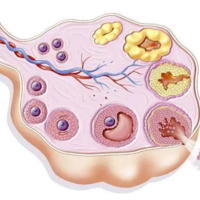

备孕是一件非常重要的事情,很多准备要孩子的夫妻都非常关心如何提高成功率。卵泡监测是备孕过程中非常常见的一种方法。但是,备孕有必要监测卵泡吗?下面我们来详细讨论一下。什么是卵泡监测卵泡监测是通过超声波或其他诊断手段,及时观察女性卵巢里的卵泡发育状况,判断卵泡大小、数量、位置、形态等指标,以便确定排卵期和最佳受孕时机。卵泡监测有哪些方法目前比较常用的卵泡监测方法有以下几种:经腹超声检查 、经阴道超声检

备孕是一件非常重要的事情,很多准备要孩子的夫妻都非常关心如何提高成功率。卵泡监测是备孕过程中非常常见的一种方法。但是,备孕有必要监测卵泡吗?下面我们来详细讨论一下。什么是卵泡监测卵泡监测是通过超声波或其他诊断手段,及时观察女性卵巢里的卵泡发育状况,判断卵泡大小、数量、位置、形态等指标,以便确定排卵期和最佳受孕时机。卵泡监测有哪些方法目前比较常用的卵泡监测方法有以下几种:经腹超声检查 、经阴道超声检

女性在平时的生活中如果不注意保养身体就很容易出现卵巢异常的情况,这种情况就会影响到女性的受孕成功率。所以有些不孕的女性会进行卵泡监测,卵泡监测可以了解清楚卵泡的生长发育。那么卵泡监测从什么时候开始?卵泡监测从什么时候开始?查卵泡配塌的时间是从月经来潮的第1天开始一直到第11天的时候。目前监测卵泡的方法主要是通过阴道彩超进行,阴道彩超的优势在于无需喝水憋尿,如果监测时没有发现优势卵泡,可间隔1到2天

卵泡监测是监测女性卵泡发育情况的的一种手段,用于确定卵子是否已经成熟,是否适合进行人工受孕或者性行为。那什么时候做卵泡监测好?测卵泡什么时候测最准大多数女性朋友为了能够顺利怀孕,都是会进行卵泡监测的,而因为对于这方面知识的欠缺,所以并不清楚自己应该在什么时候去进行卵泡监测才能得到最准确的结果,那么你知道什么时槐信候测卵泡最准吗?下面我们就来看看问题的答案吧。卵泡发育从月经第一天开始,进入卵泡期,逐